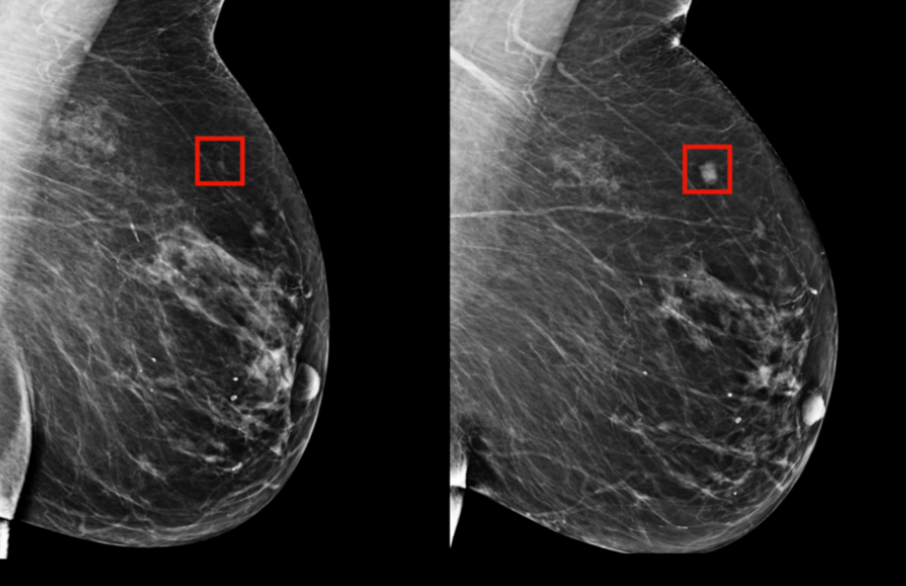

使用AI技术来检测乳腺癌,如今已有诸多研究,但大多是基于磁共振、乳腺X线影像进行预测。而超声是中国女性乳腺癌筛查的主要方式。如何利用好超声影像,进行乳腺癌筛查,并对乳腺癌做分子亚型分类,是中国AI医疗领域一个重要且有待拓展的方向。

清华大学、北京智源人工智能研究院以及北京协和医院的研究团队在这一方向进行合作,在2020年 6月份曾发布一项基于VGG模型,对超声影像进行良/恶性检测 及分子亚型分类的深度神经网络模型SonoBreast,当时模型在乳腺癌分子分型上的准确率为56.3%,F1 Score为45.8%。

研究团队经过数月对数据集预处理算法和训练模型的改进,根据近期公布结果,这一模型的分子分型准确率提升了近20个点,达到 76%;而在二分类问题上可以达到93%的准确率。

清华大学、智源研究院和协和医院合作开发的SonoBreast模型,利用超声影像预测乳腺癌分子亚型,准确率提升至76%,有助于无创、快速的临床决策。该模型通过深度学习技术,尤其是VGG-19网络,处理超声图像,改善数据预处理方法,以实现更精准的预测。未来计划通过联邦学习扩大数据集,并举办机器学习竞赛推动研究进展。

清华大学、智源研究院和协和医院合作开发的SonoBreast模型,利用超声影像预测乳腺癌分子亚型,准确率提升至76%,有助于无创、快速的临床决策。该模型通过深度学习技术,尤其是VGG-19网络,处理超声图像,改善数据预处理方法,以实现更精准的预测。未来计划通过联邦学习扩大数据集,并举办机器学习竞赛推动研究进展。